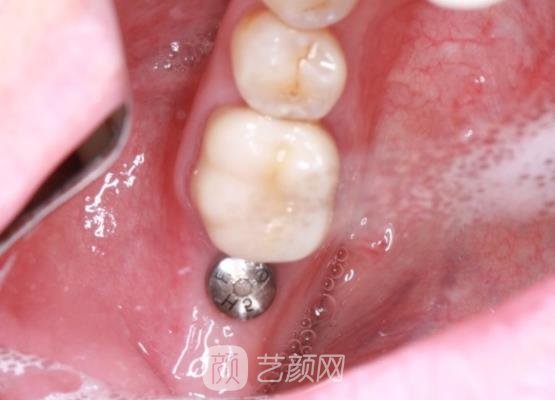

接下来医生又询问了我的身体情况,然后对我的口腔问题进行了全方面的检查,通过拍口腔全片,按照我的牙齿大小和口腔情况帮我制定了适合我的种植牙手术方案。

方案确定好以后手术就开始了,手术刚开始的时候我也是比较紧张的,不过看到医生的手术操作手法是比较娴熟和专业的,我也就放心了很多,手术的过程是比较快的,几个小时就完成了。

刚结束手术的时候,我的牙龈处有着一些肿胀的情况,而且还有一些疼痛的感觉,医生告诉我这些情况比较正常,过不了几天就会自动消退,如果几天以后还存在着异样的情况,就让我及时的与他取得联系进行复诊。

一个月以后,我的种植牙已经恢复好了,而且口腔里边也没有一些异物的感觉,成果真的是很好的,就像是我自己的牙齿一样,对于手术我也是比较满意的。